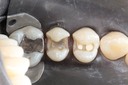

Frank Fukuda #30 pre-op

Frank Fukuda #30 caries removal

Frank Fukuda #30 buccal prep

Frank Fukuda #30 prep